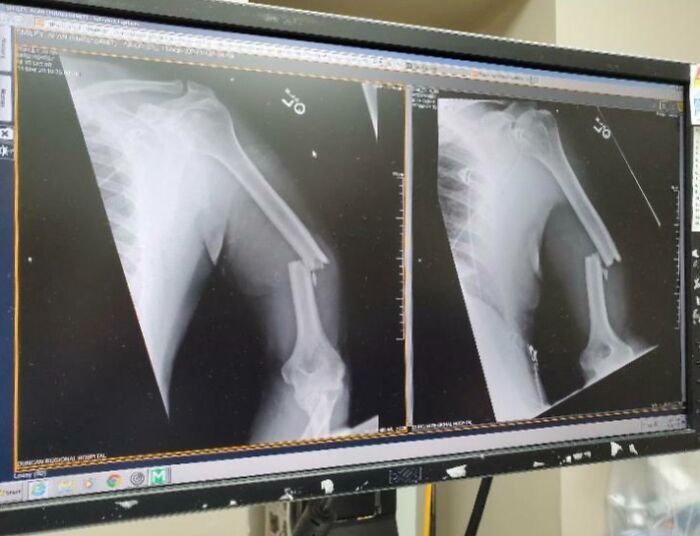

Good Thing I Did This While Working In The Emergency Room